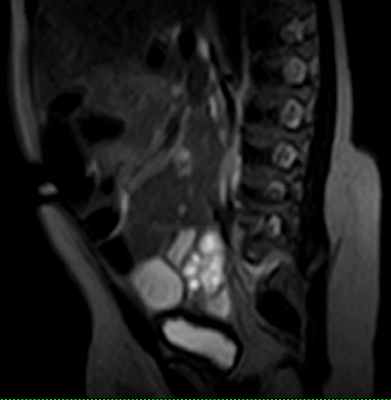

24.07.2012 г. МРТ пояснично-крестцового отдела позвоночника девочка 2 мес Липомиеломенингоцеле. КОНКУРС.

На МРТ пояснично-крестцового отдела определяяетмя подкожная липома , к оторая через дефект (ращепление) дужек сакральных позвонков распространяетя в позвоночный канал, соединяеясь на этом уровне с аномально низко расположеным спинном мозгм (Tethered spinal cord syndrome). Также мы видим выхождение спинного мозга и оболочек через дефект дужек сакральных позввонков. Такая врожденная аномалия развития позвоночника и спинного мозга называется - ЛИПОМИЕЛОМЕНИНГОЦЕЛЕ.(вариант спинального дизарфизма).

КТ/миелография или МРТ могут выявить ненормально низко расположенный конус. МРТ также показывает жировое объемное образование (высокий сигнал в режиме Т1, низкий в режиме Т2).